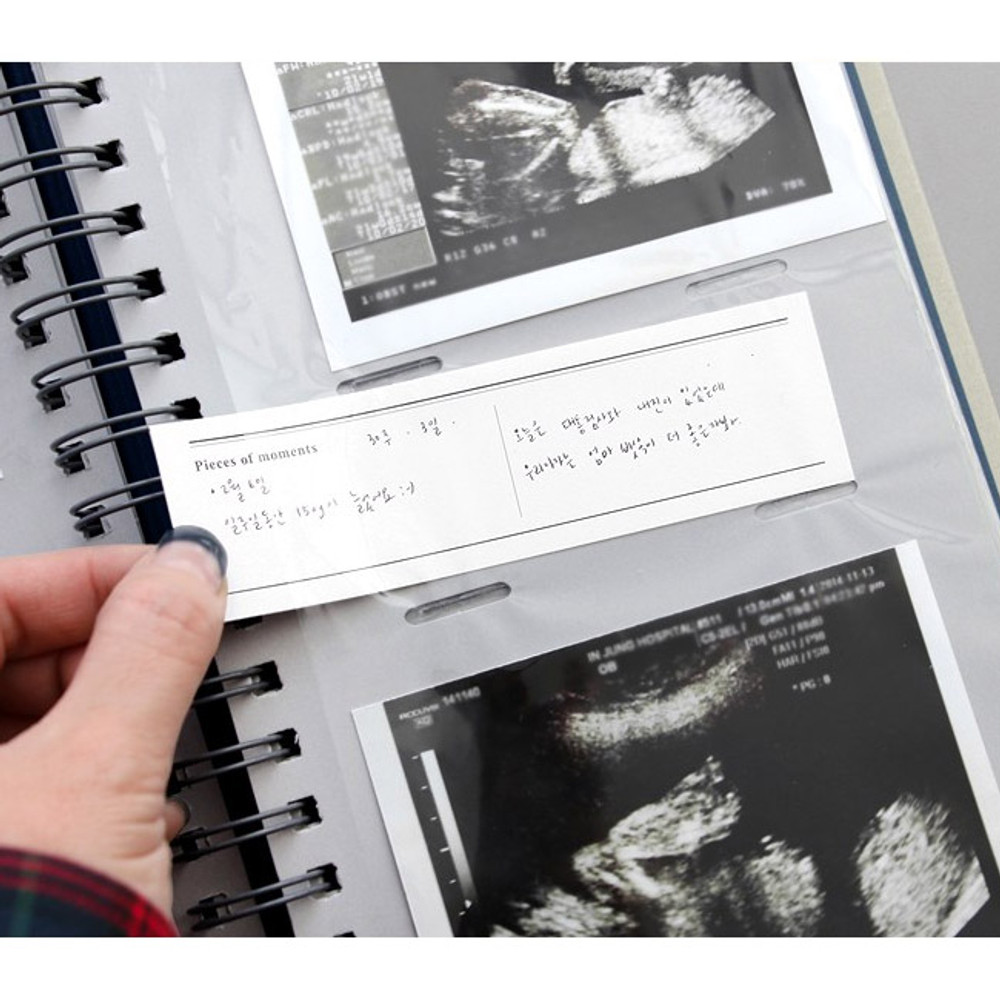

Iconic Album de photos 3X5 slip in photo album by ICONIC. The Album de photos photo album is a well made and useful slip in album. This photo album allows you to store up to 100 photos by inserting them into these frames. A purchase also includes white label papers. Keep your precious stories forever with this album.